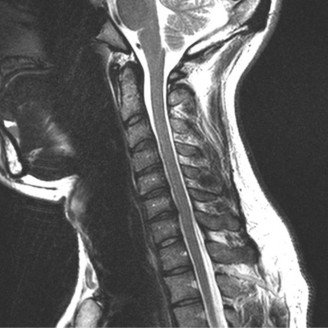

Pre-Operative Planning, Templating, and Patient Positioning

When surgical intervention becomes unavoidable, meticulous pre-operative planning is the cornerstone of a successful outcome. Advanced imaging is non-negotiable. An MRI with and without gadolinium contrast is the gold standard for defining the extent of the epidural abscess, the degree of neural compression, and the involvement of adjacent paraspinal musculature (e.g., psoas abscess). T1-weighted images typically show hypointense signals in the infected marrow, while T2-weighted and STIR sequences reveal hyperintense fluid and edema in the disc space and vertebral bodies. Gadolinium enhancement highlights the vascularized inflammatory phlegmon and the capsule of any abscesses.

In addition to MRI, a fine-cut computed tomography (CT) scan is essential for evaluating bony destruction. CT allows the surgeon to assess bone stock for pedicle screw purchase and to template the size of the interbody cages required for anterior column reconstruction. Upright standing radiographs (if the patient can tolerate them) or full-length supine films are necessary to evaluate global spinal alignment and regional kyphosis.